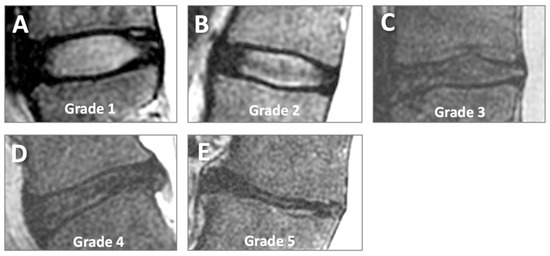

- Chen, K.C.; Tran, B.; Biswas, R.; Statum, S.; Masuda, K.; Chung, C.B.; Bae, W.C. Evaluation of the disco-vertebral junction using ultrashort time-to-echo magnetic resonance imaging: Inter-reader agreement and association with vertebral endplate lesions. Skelet. Radiol. 2016, 45, 1249–1256. [Google Scholar] [CrossRef] [PubMed]

- Law, T.; Anthony, M.P.; Chan, Q.; Samartzis, D.; Kim, M.; Cheung, K.M.; Khong, P.L. Ultrashort time-to-echo MRI of the cartilaginous endplate: Technique and association with intervertebral disc degeneration. J. Med. Imaging Radiat. Oncol. 2013, 57, 427–434. [Google Scholar] [CrossRef] [PubMed]

- Ji, Z.; Li, Y.; Dou, W.; Zhu, Y.; Shi, Y.; Zou, Y. Ultra-short echo time MR imaging in assessing cartilage endplate damage and relationship between its lesion and disc degeneration for chronic low back pain patients. BMC Med. Imaging 2023, 23, 60. [Google Scholar] [CrossRef]

- Finkenstaedt, T.; Siriwananrangsun, P.; Masuda, K.; Bydder, G.M.; Chen, K.C.; Bae, W.C. Ultrashort time-to-echo MR morphology of cartilaginous endplate correlates with disc degeneration in the lumbar spine. Eur. Spine J. 2023, 32, 2358–2367. [Google Scholar] [CrossRef]